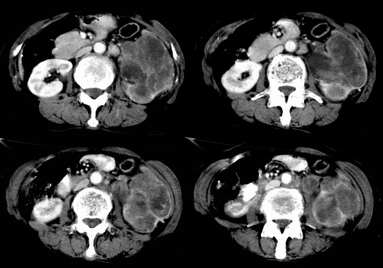

病患,女,69岁,左侧腰部不适,偶感疼痛2个月余,无化验室检查,行彩超发现左侧肾区实质性肿物,后行ct检查,结果同上。

左肾不规则软组织肿块,内见低密度坏死区,与正常肾实质分界不清,左肾明显增大,增强呈不规则条索状强化,肾盂及左输尿管上段扩张。肾周脂肪层受侵、模糊。印象:典型左肾癌。

平扫,表现为肾实质肿块,呈分叶状,肿块密度不均,内有不规则低密度区(陈旧性出血?坏死?)有的似呈囊性,增强明显不均一强化,与肾实质相比呈相对低密度的不均一肿块,肾周脂肪间隙可见,肾前筋膜未见增后,肾血管及腹主动脉旁未见肿大淋巴结影